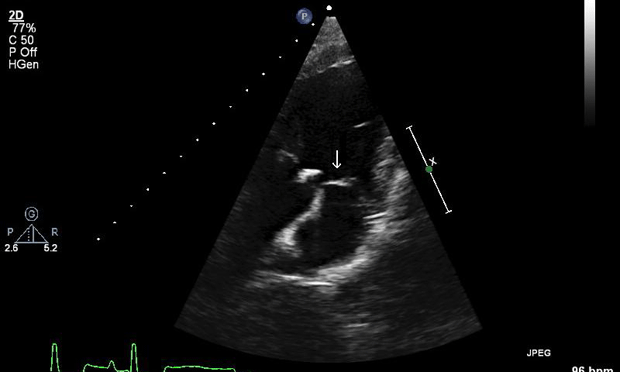

Imaging ResultsThoracic radiographs and abdominal ultrasound were unremarkable. Two-dimensional, M-mode, color flow, and spectral Doppler echocardiography demonstrated a vegetative lesion associated with the aortic valve, moderate aortic regurgitation, mild thickening of the mitral valve, and mild left atrial enlargement (Figures 1 and 2).

Figure 1 (above): Left parasternal long-axis view: A hyperechoic lesion associated with the aortic valve was noted (arrow), consistent with a vegetative endocarditis lesion.